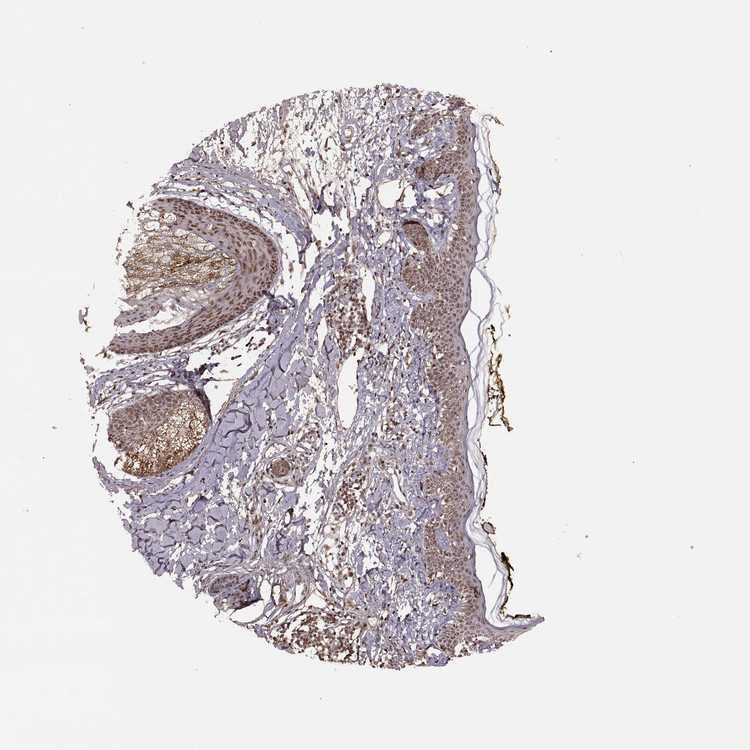

SKIN 1 - Antibody stainingi

Antibody staining in the annotated cell types in the current human tissue is reported as not detected, low, medium, or high, based on conventional immunohistochemistry profiling in selected tissues. This score is based on the combination of the staining intensity and fraction of stained cells.

Each image is clickable and will lead to virtual microscopy that enables deeper exploration of all samples and also displays staining intensity scores, fraction scores and subcellular localization as well as patient and tissue information for each sample.

Antibody HPA069022

Langerhans Medium

Fibroblasts Medium

Keratinocytes Medium

Melanocytes Medium